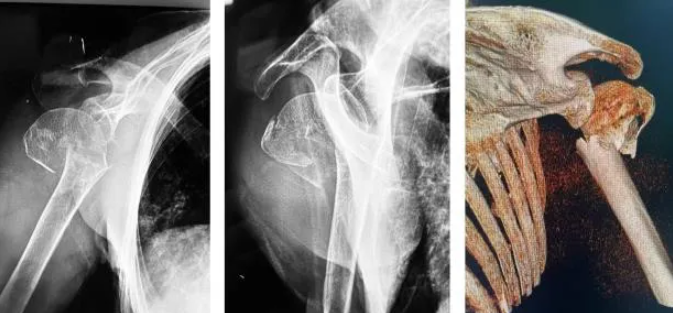

在 X 光机的持续照射下,医生们通过几个微小的切口,精准地将钢板和螺钉植入骨折部位。每一个动作都必须稳、准、轻,在影像的指引下分毫不差。

骨科团队决定采用微创内固定手术。但对医生提出了更高要求:手术必须在 X 射线的实时引导下完成。这意味着,医务人员将长时间暴露在辐射环境中。